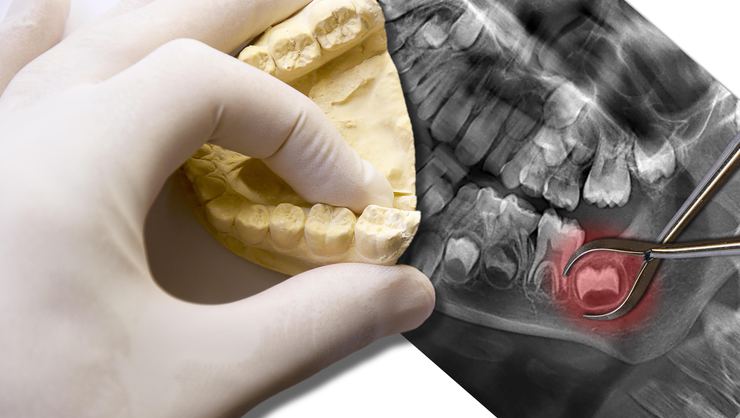

İmplant mı, Geleneksel Köprü Protez mi? Eksik Diş Tedavisinde Karar Rehberi

Gülüşünüzdeki boşluklar sadece estetiği bozmaz. Çiğneme kalitenizi ve konuşma fonksiyonlarınızı da oldukça olumsuz etkiler. İnsanlar eksik dişleri yüzünden özgüven kaybı […]